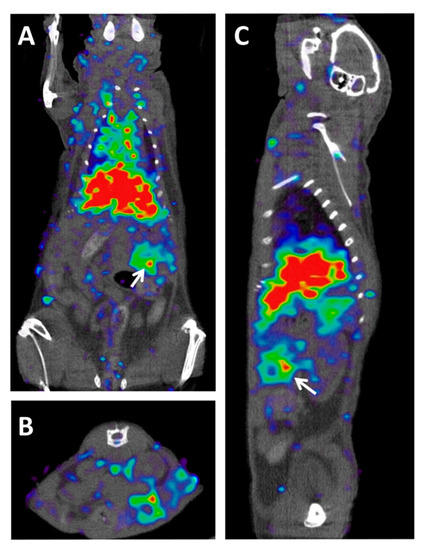

- Morcillo, M.Á.; De Lucas, Á.G.; Oteo, M.; Romero, E.; Magro, N.; Ibáñez, M.; Martínez, A.; Garaulet, G.; Arroyo, A.G.; López-Casas, P.P.; et al. MT1-MMP as a PET Imaging Biomarker for Pancreas Cancer Management. Contrast Media Mol. Imaging 2018, 2018. [Google Scholar] [CrossRef]

| [89Zr]Zr-Df-LEM2/15 (anti-MM1-MMP mAb) | Lysine-based random | MT1-MMP | Metalloprotease MT1-MMP is overexpressed in many tumors and associates with tumor growth, invasion, metastasis, and poor prognosis | Subcutaneous xenograft mouse model with Capan-2 cells, and subcutaneous and orthotopic PDX mice. | [107] |